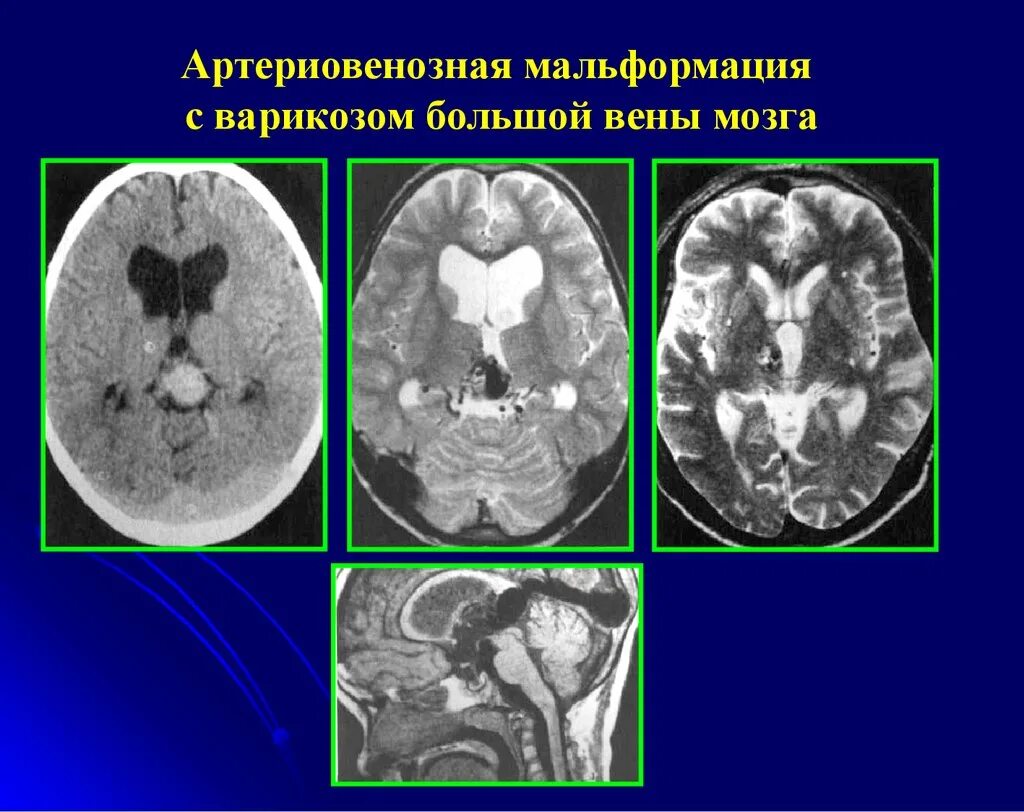

Что такое мальформация головного мозга